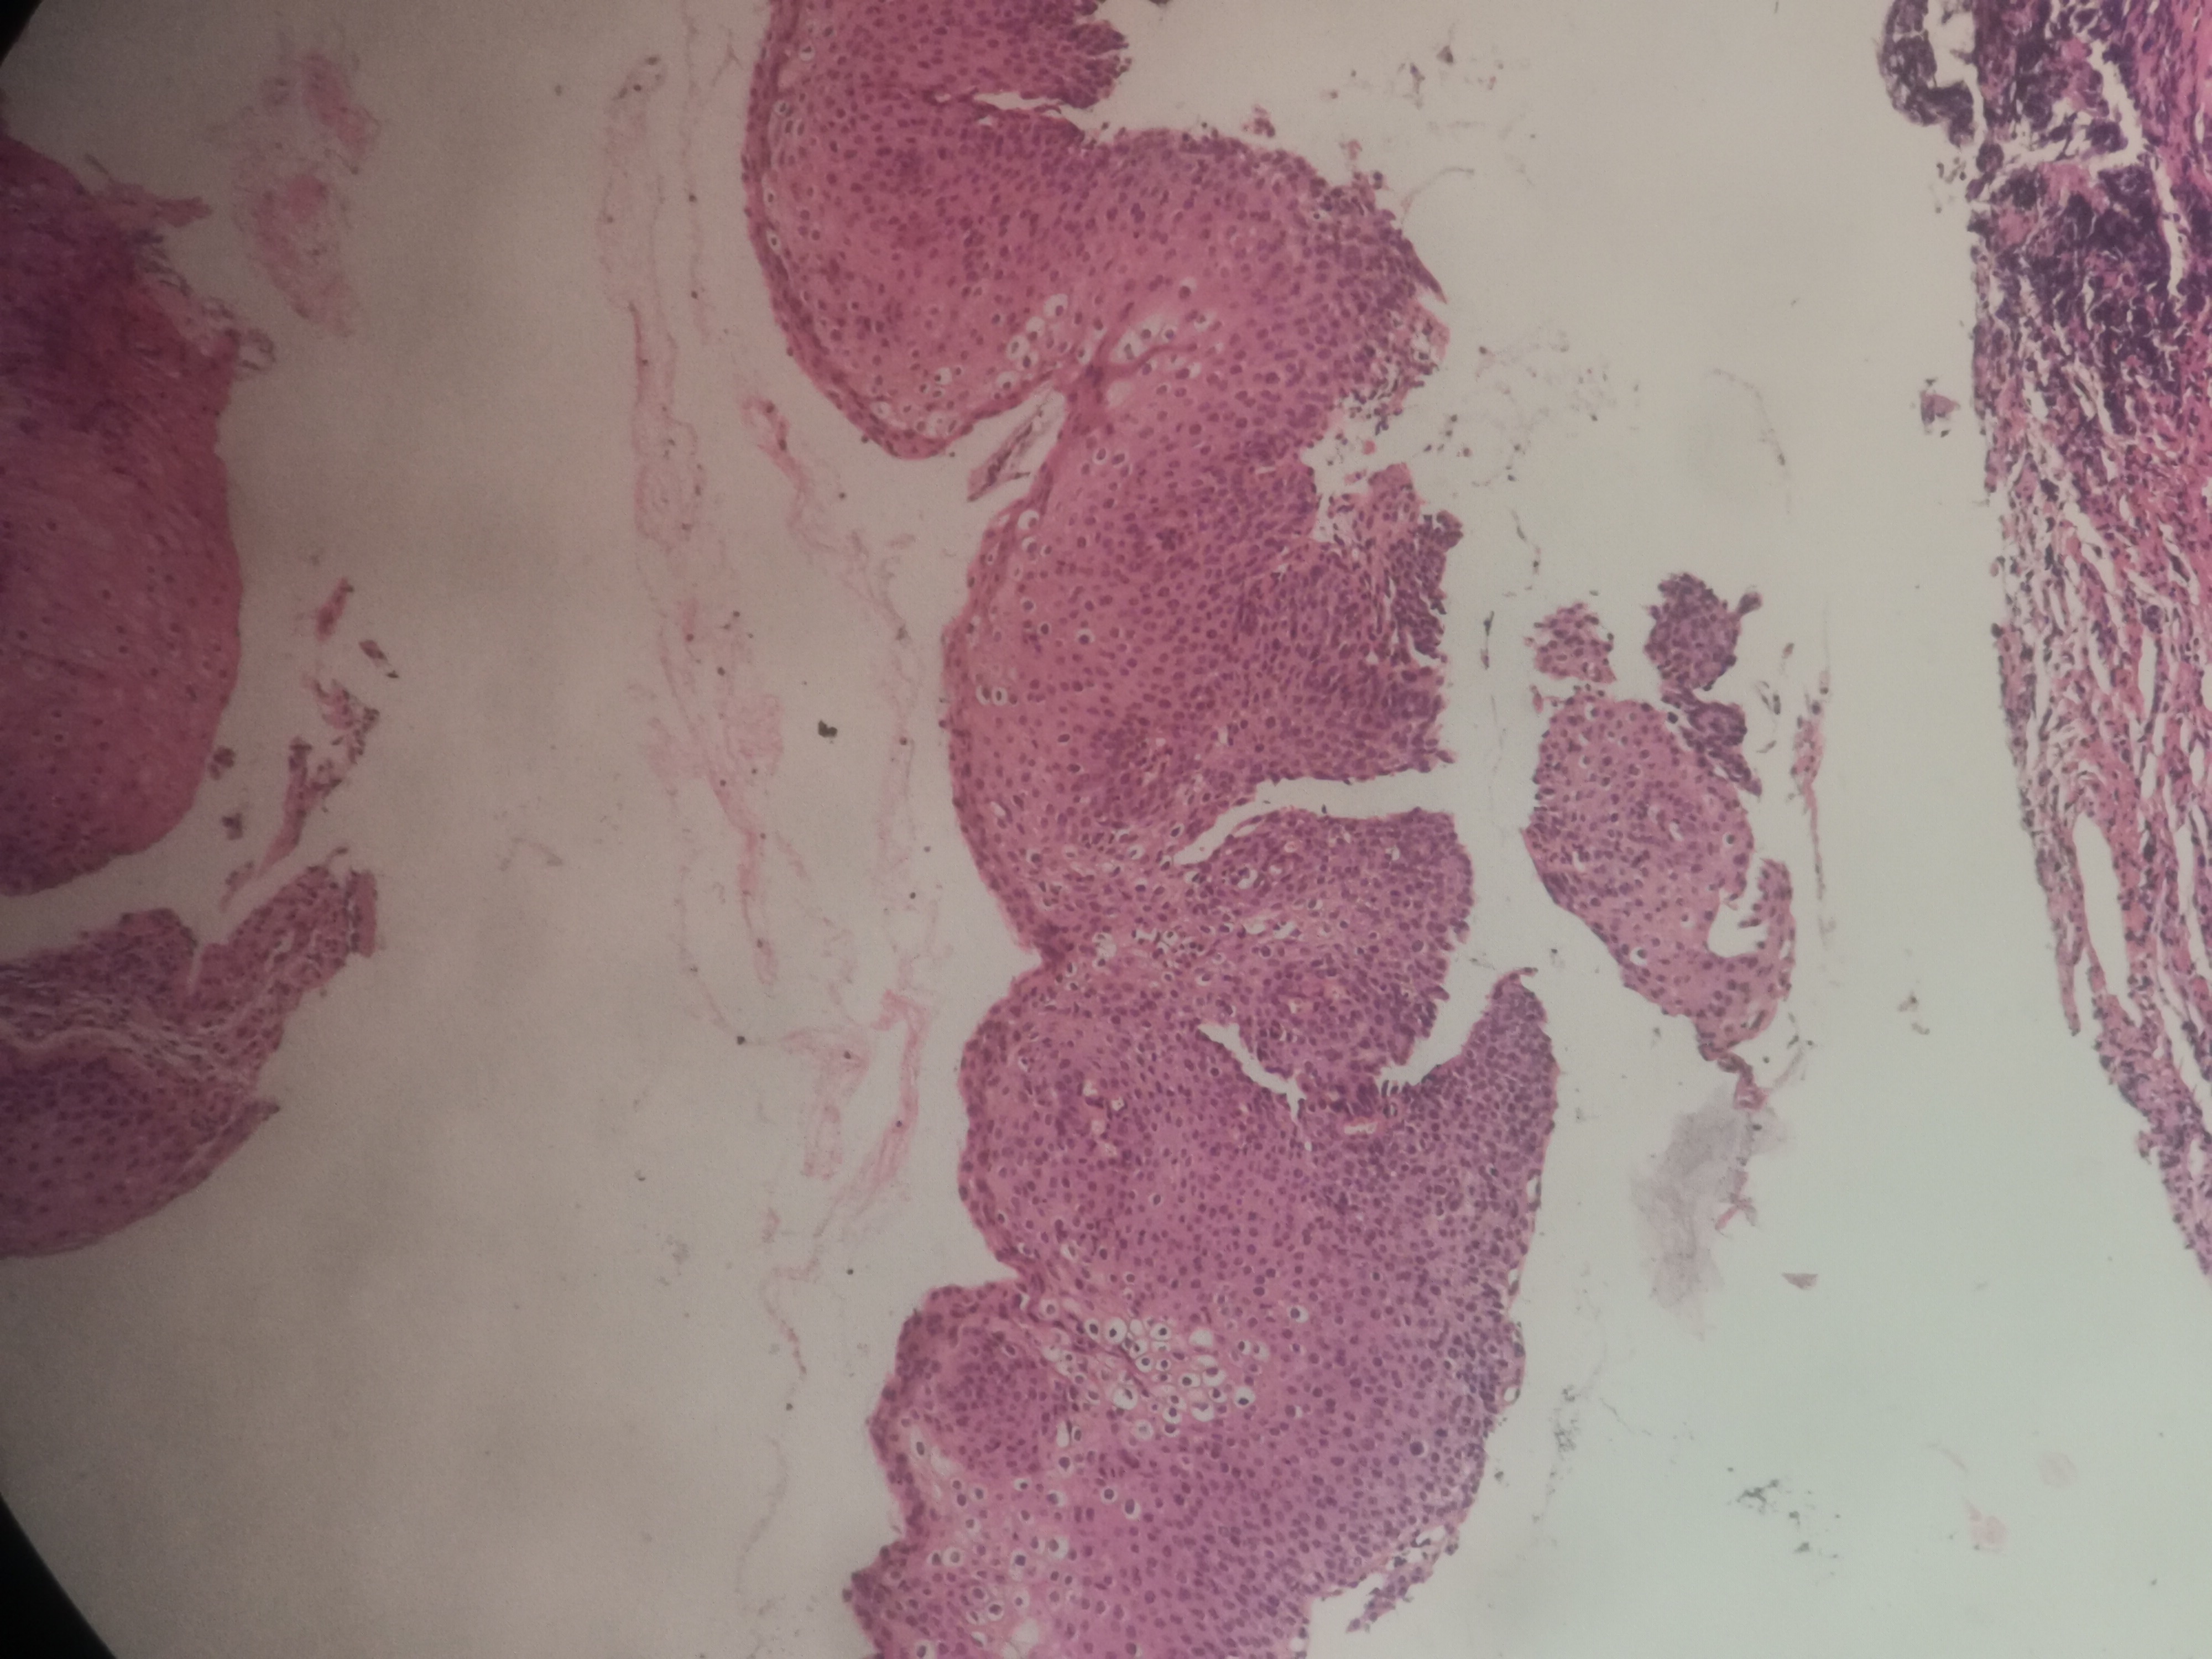

急!请老师帮忙看看,12点够CINii吗,还是报CINI~II

性别

女

年龄

59岁

临床诊断

HPV感染

一般病史

HPV16(+)

标本名称

宫颈活检组织

大体所见

3点:0.8x0.4x0.3厘米1块。6点0.7x0.6x0.3厘米1块。9点0.6x0.6x0.4厘米1块。12点0.8x0.5x0.3厘米,0.6x0.6x0.4厘米2块。

图1~16为12点2块组织,图17为9点组织,图18,为6点组织,图19为3点组织。

倾向低级别,标记看看